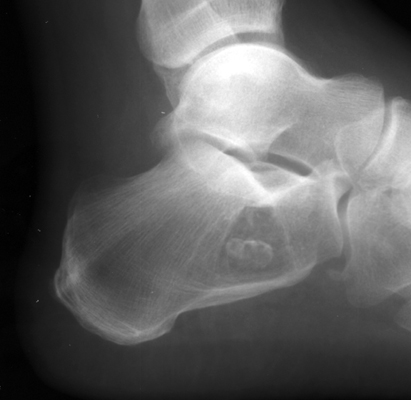

Diagnosis:Intraosseous lipoma Discussion:A classic appearance of intraosseous lipoma of the calcaneus is the presence of a well defined lytic lesion with a central calcification resembling a cockade. A cockade is badge, usually in the form of a rosette, or knot, and generally worn upon the hat. References: